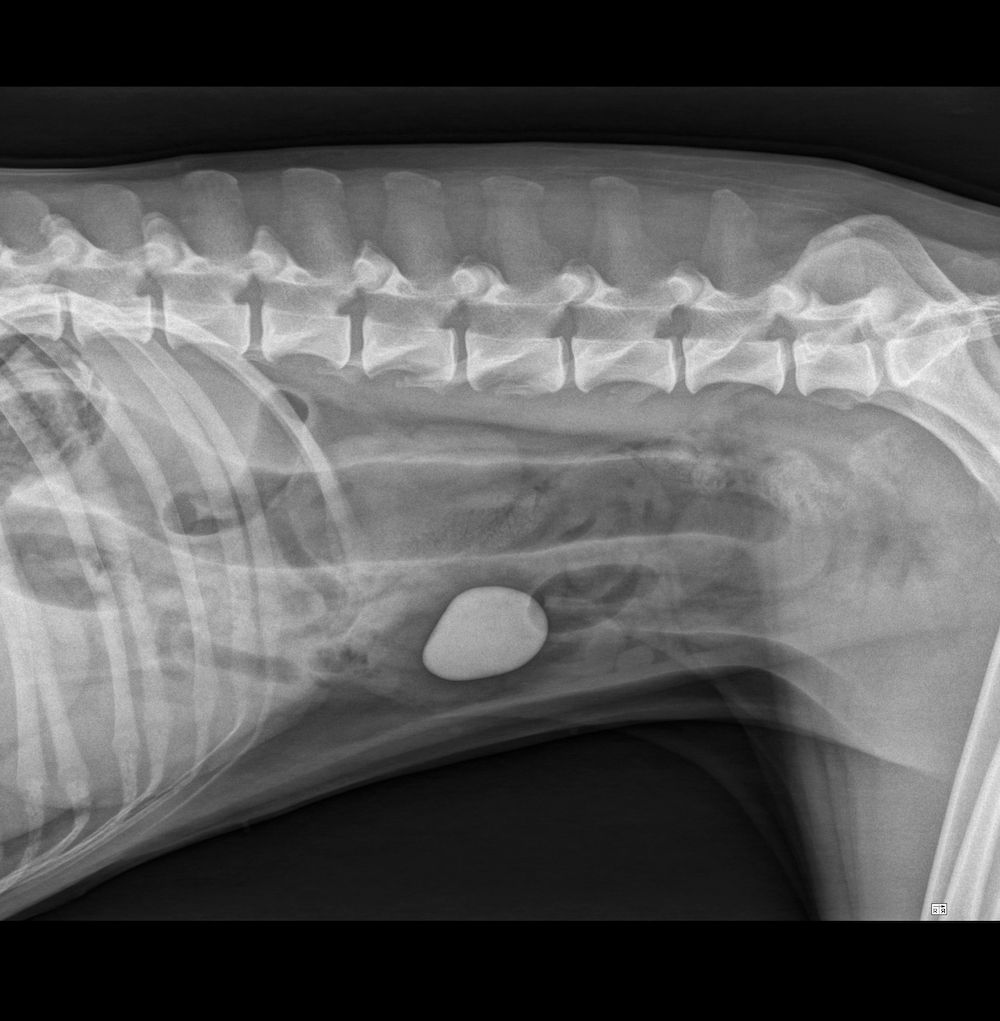

X-Ray Vision

How foreign bodies appear on radiograph